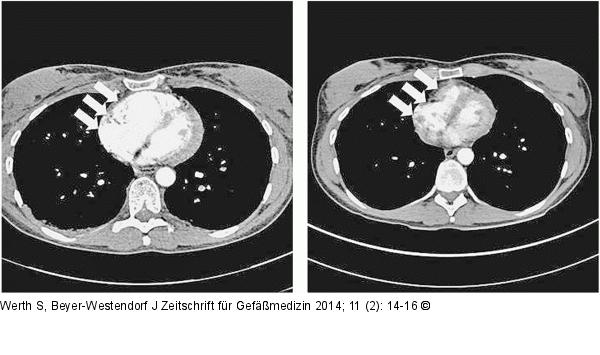

Abbildung 4a-b: Rechtsherzbelastung Rechtsherzbelastung mit massiver rechtsventrikulärer Dilatation auf 40 mm in der Akutphase (linkes Bild; Pfeile) und CT-Verlaufskontrolle nach 6 Monaten mit nun wieder normal großem (28 mm) und tailliertem rechten Ventrikel (rechtes Bild; Pfeile) |

Rechtsherzbelastung mit massiver rechtsventrikulärer Dilatation auf 40 mm in der Akutphase (linkes Bild; Pfeile) und CT-Verlaufskontrolle nach 6 Monaten mit nun wieder normal großem (28 mm) und tailliertem rechten Ventrikel (rechtes Bild; Pfeile) |